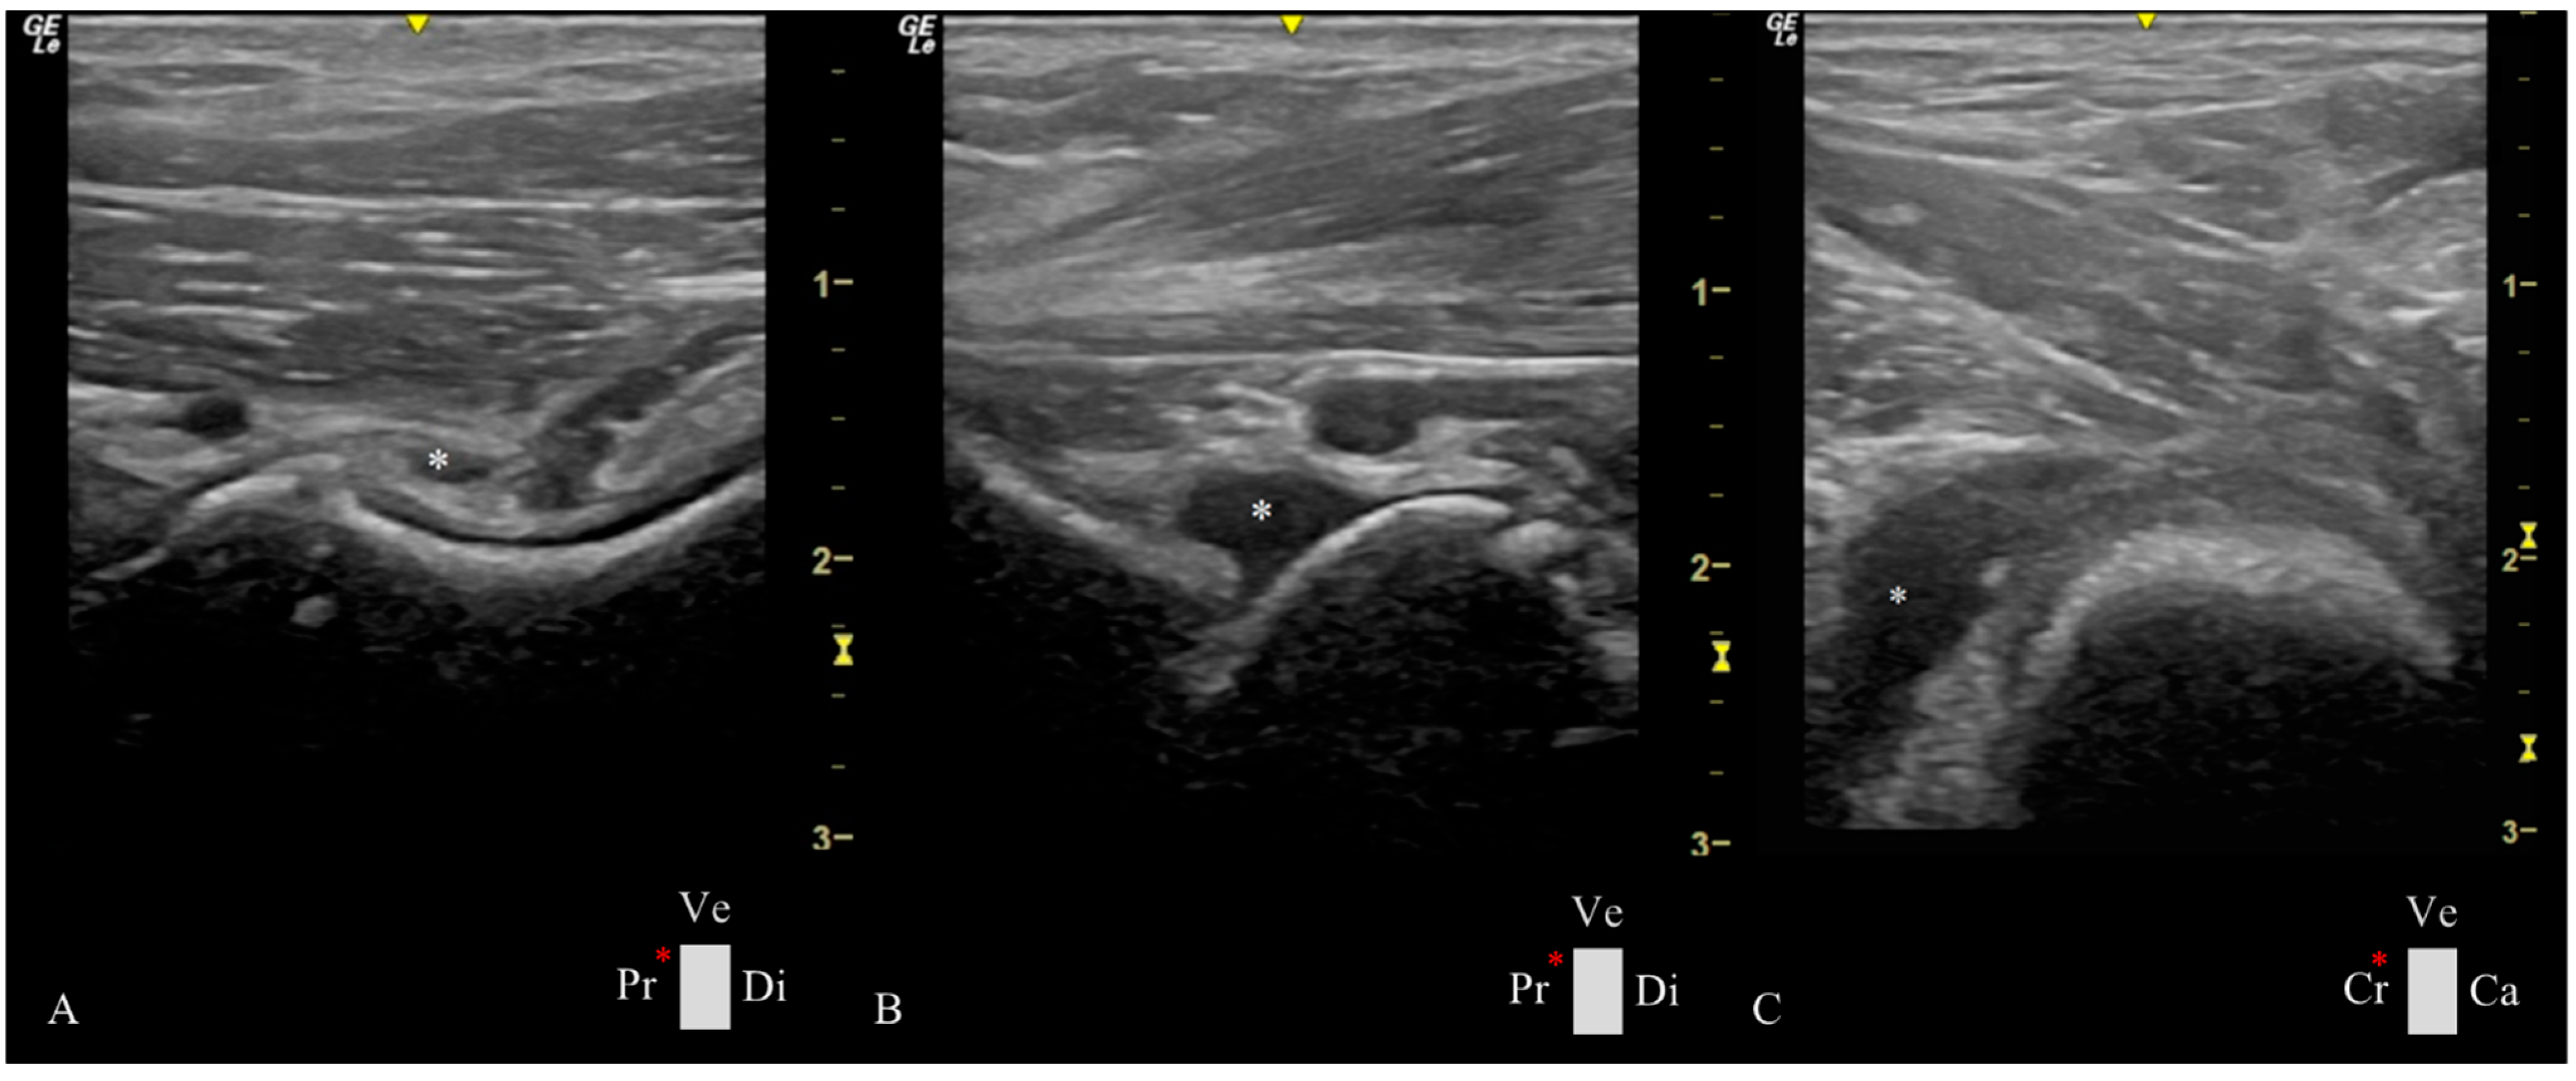

- Longitudinal Femoral Head–Neck Plane

- Transverse Femoral Head–Neck Plane

2.4. Ultrasonographic Hip Joint Measurements